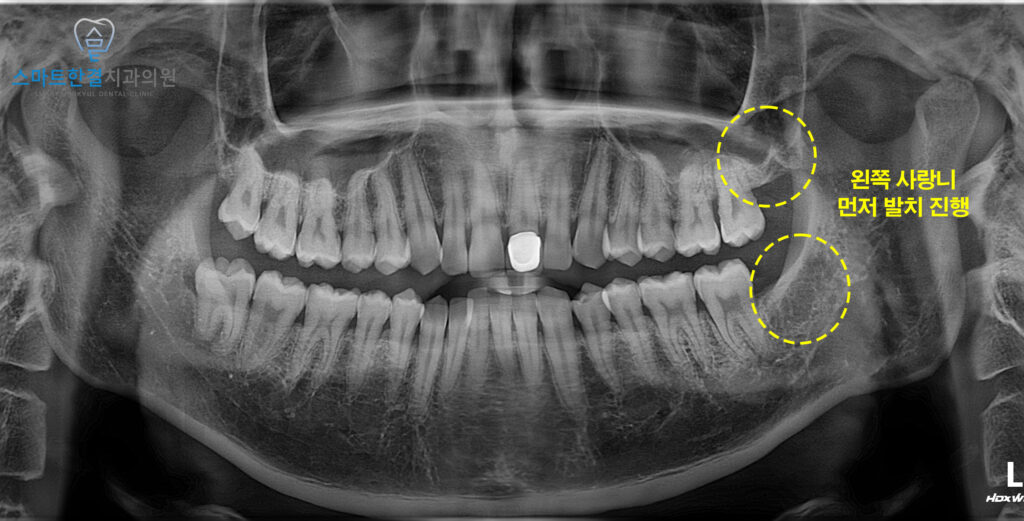

파노라마 엑스레이 사진을 통해

확인해 보니,

네 개의 사랑니 모두 비교적

정상적인 형태로 자라고 있었지만,

아래쪽 사랑니는 다른 치아와 달리

약간 턱뼈 쪽으로 기울어진 상태였어요.

이런 경우에는 필요시 주변 뼈를

일부 다듬는 과정이

추가될 수 있다는 점을

함께 설명드렸어요.